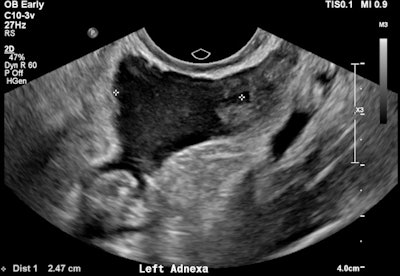

A 32-year-old female presented with severe constant left lower abdominal pain, per vaginal spotting and nausea. A pelvic ultrasound performed at six weeks' gestation demonstrated a viable intrauterine gestation and a small perigestational hematoma. A heterogeneous mass was noted abutting the left ovary. It featured peripheral vascularity, but no internal vascularity. There was small-volume pelvic free fluid with low-level internal echoes consistent with hemoperitoneum (see three images below).

Left adnexal heterogeneous mass with an echogenic tubal ring sign (blue arrows) adjacent to the left ovary (red arrows).

Pelvic free fluid with low-level internal echoes consistent with hemoperitoneum.The patient was given a preliminary diagnosis of a hemorrhagic corpus luteal cyst. Heterotopic pregnancy was initially considered but thought less likely. The treating team opted for conservative management with a view to perform short-term follow-up ultrasound. Follow-up imaging two days later demonstrated a persistent left adnexal mass with interval increase in hemoperitoneum volume. The mass was seen to move separately to the left ovary on transvaginal/abdominal palpation maneuvers.